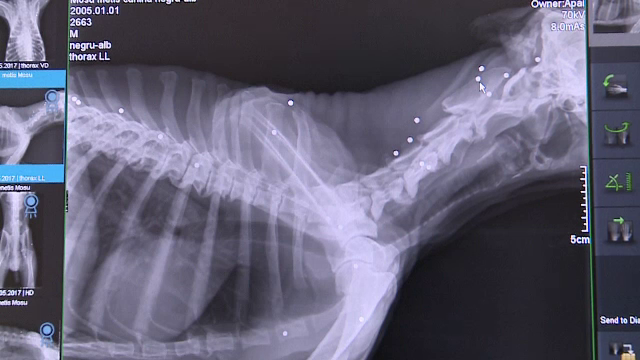

A fost impuscat cu 27 de alice si agoniza de ceva vreme pe marginea drumului. Cainele a fost operat, insa starea lui nu este buna deloc. Deocamdata nu se cunosc nici proprietarii si nici cei care au fost capabili de asemenea fapte.

Cand a fost gasit, cainele nu mancase de cateva zile. Nu parea sa aiba rani, insa cand l-a consultat veterinarul a constatat ca avea trupul plin de alice. Medicii l-au operat si au scos trei dintre ele.

Wili Glaser, medic veterinar: "Problema lui este intoxicatia cu plumb. In general, alicele care sunt in apropierea sistemului nervos pot da simptome cum le are el si cum reiese din analize intoxicatia cu plumb. Asta este cea mai grava, nu alicele. Si a fost impuscat mai de mult timp. Este foarte slab, numai piele si os. Daca ar fi fost gasit in prima faza, era si mai usor de extras toate alicele"